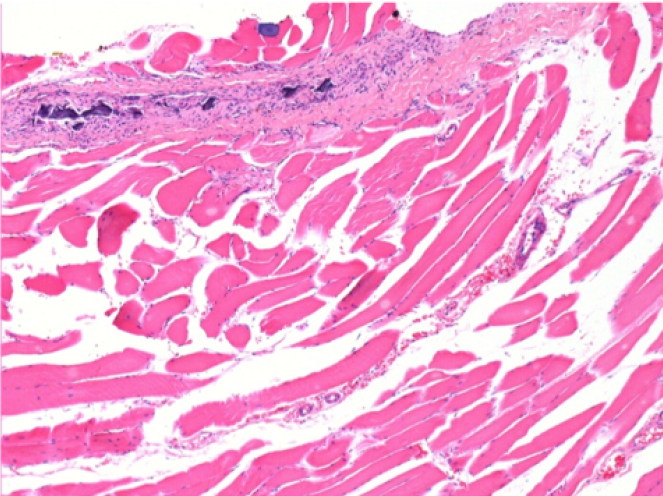

10 días después de la inyección de Endopeel

10 días después de la inyección de Endopeel 0,1 ml en el músculo pretibial derecho.

Aquí puede ver la formación de las vacuolas que están rodeadas de linfocitos. Las vacuolas son diferentes a la necrosis tisular. La presencia de linfocitos está relacionada con la permeabilidad de las membranas celulares.

L : Control-100xD10

R:100xD10

R :200xD10

R :400xD10